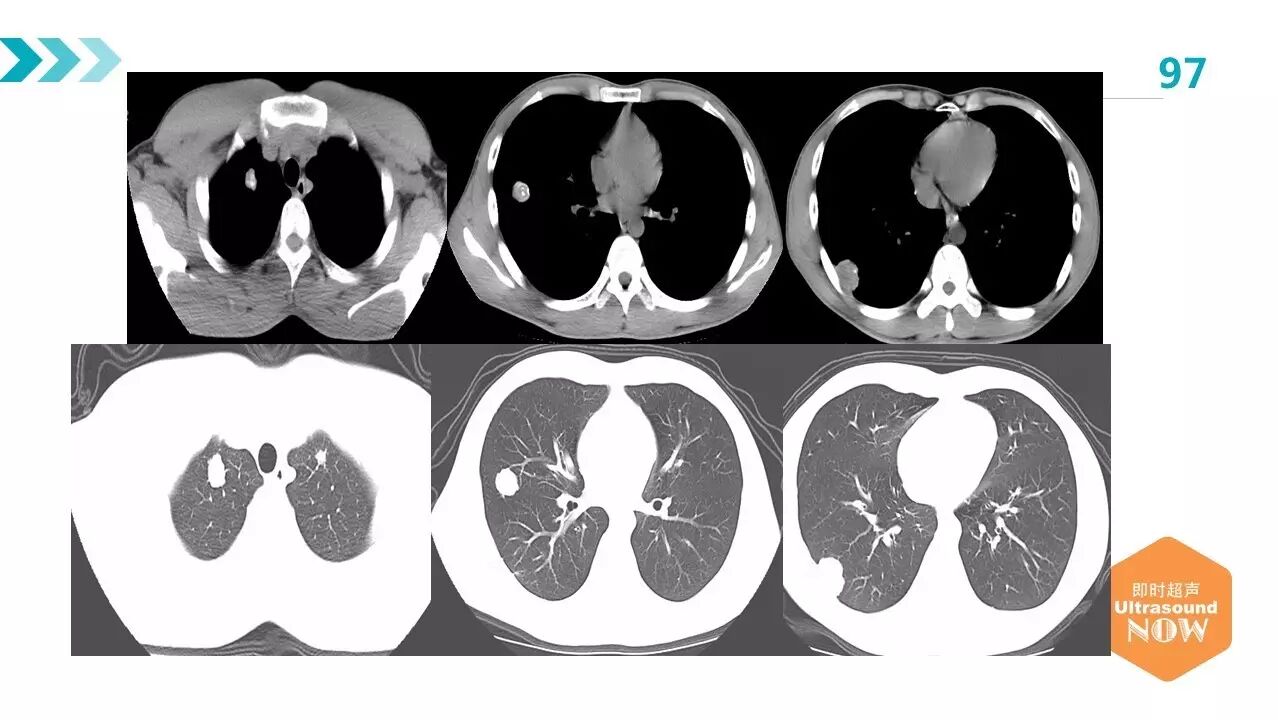

肺包虫病一例——黄超,新疆职业病医院

图片尺寸2638x1200